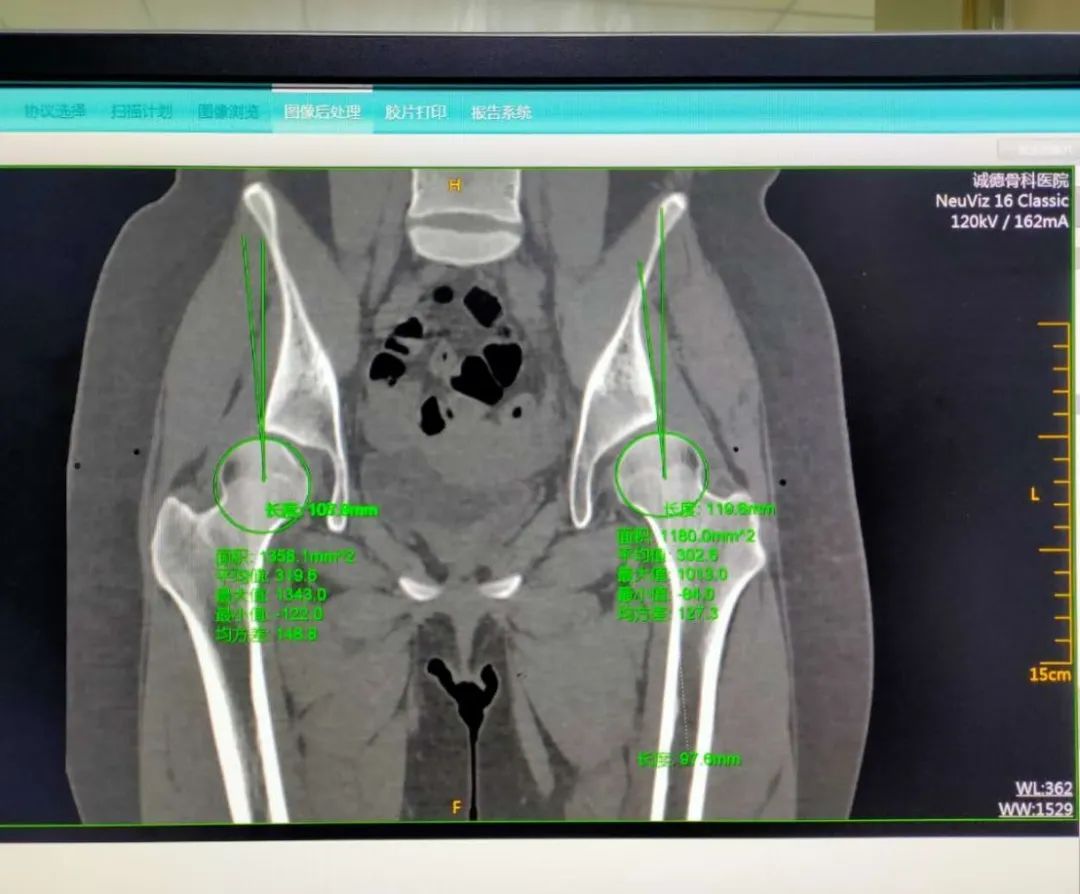

今年15歲的孫某,出現(xiàn)雙側(cè)髖部疼痛,呈持續(xù)性隱痛,只采取口服藥物的保守治療,但是疼痛未見減輕反而愈演愈烈,于是到誠德骨科醫(yī)院集團(tuán)(市中院區(qū))尋求專家的幫助,經(jīng)過多方檢查和論證后,劉德俊院長診斷為:

先天性多發(fā)性骨骺發(fā)育不良,并決定為其實(shí)施“髖臼周圍截骨術(shù)”。

據(jù)了解,髖關(guān)節(jié)發(fā)育不良是引起繼發(fā)性髖關(guān)節(jié)炎的重要致病因素之一,髖臼周圍截骨術(shù)能夠有效改善髖臼覆蓋、增加負(fù)重關(guān)節(jié)面,內(nèi)移髖關(guān)節(jié)的旋轉(zhuǎn)中心,從而減小髖關(guān)節(jié)負(fù)重面軟骨應(yīng)力,達(dá)到預(yù)防和推遲骨關(guān)節(jié)炎發(fā)生的目的。